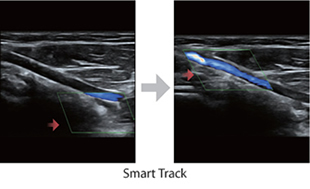

Smart Track

La herramienta Smart Track proporciona una optimización inteligente de la imagen ecográfica vascular con el simple gesto de presionar un botón. Optimiza el espectro del modo de Color, Power y PW, gracias al seguimiento automático, reduciendo y simplificando el flujo de trabajo en exámenes vasculares y ofreciendo una imagen óptima.